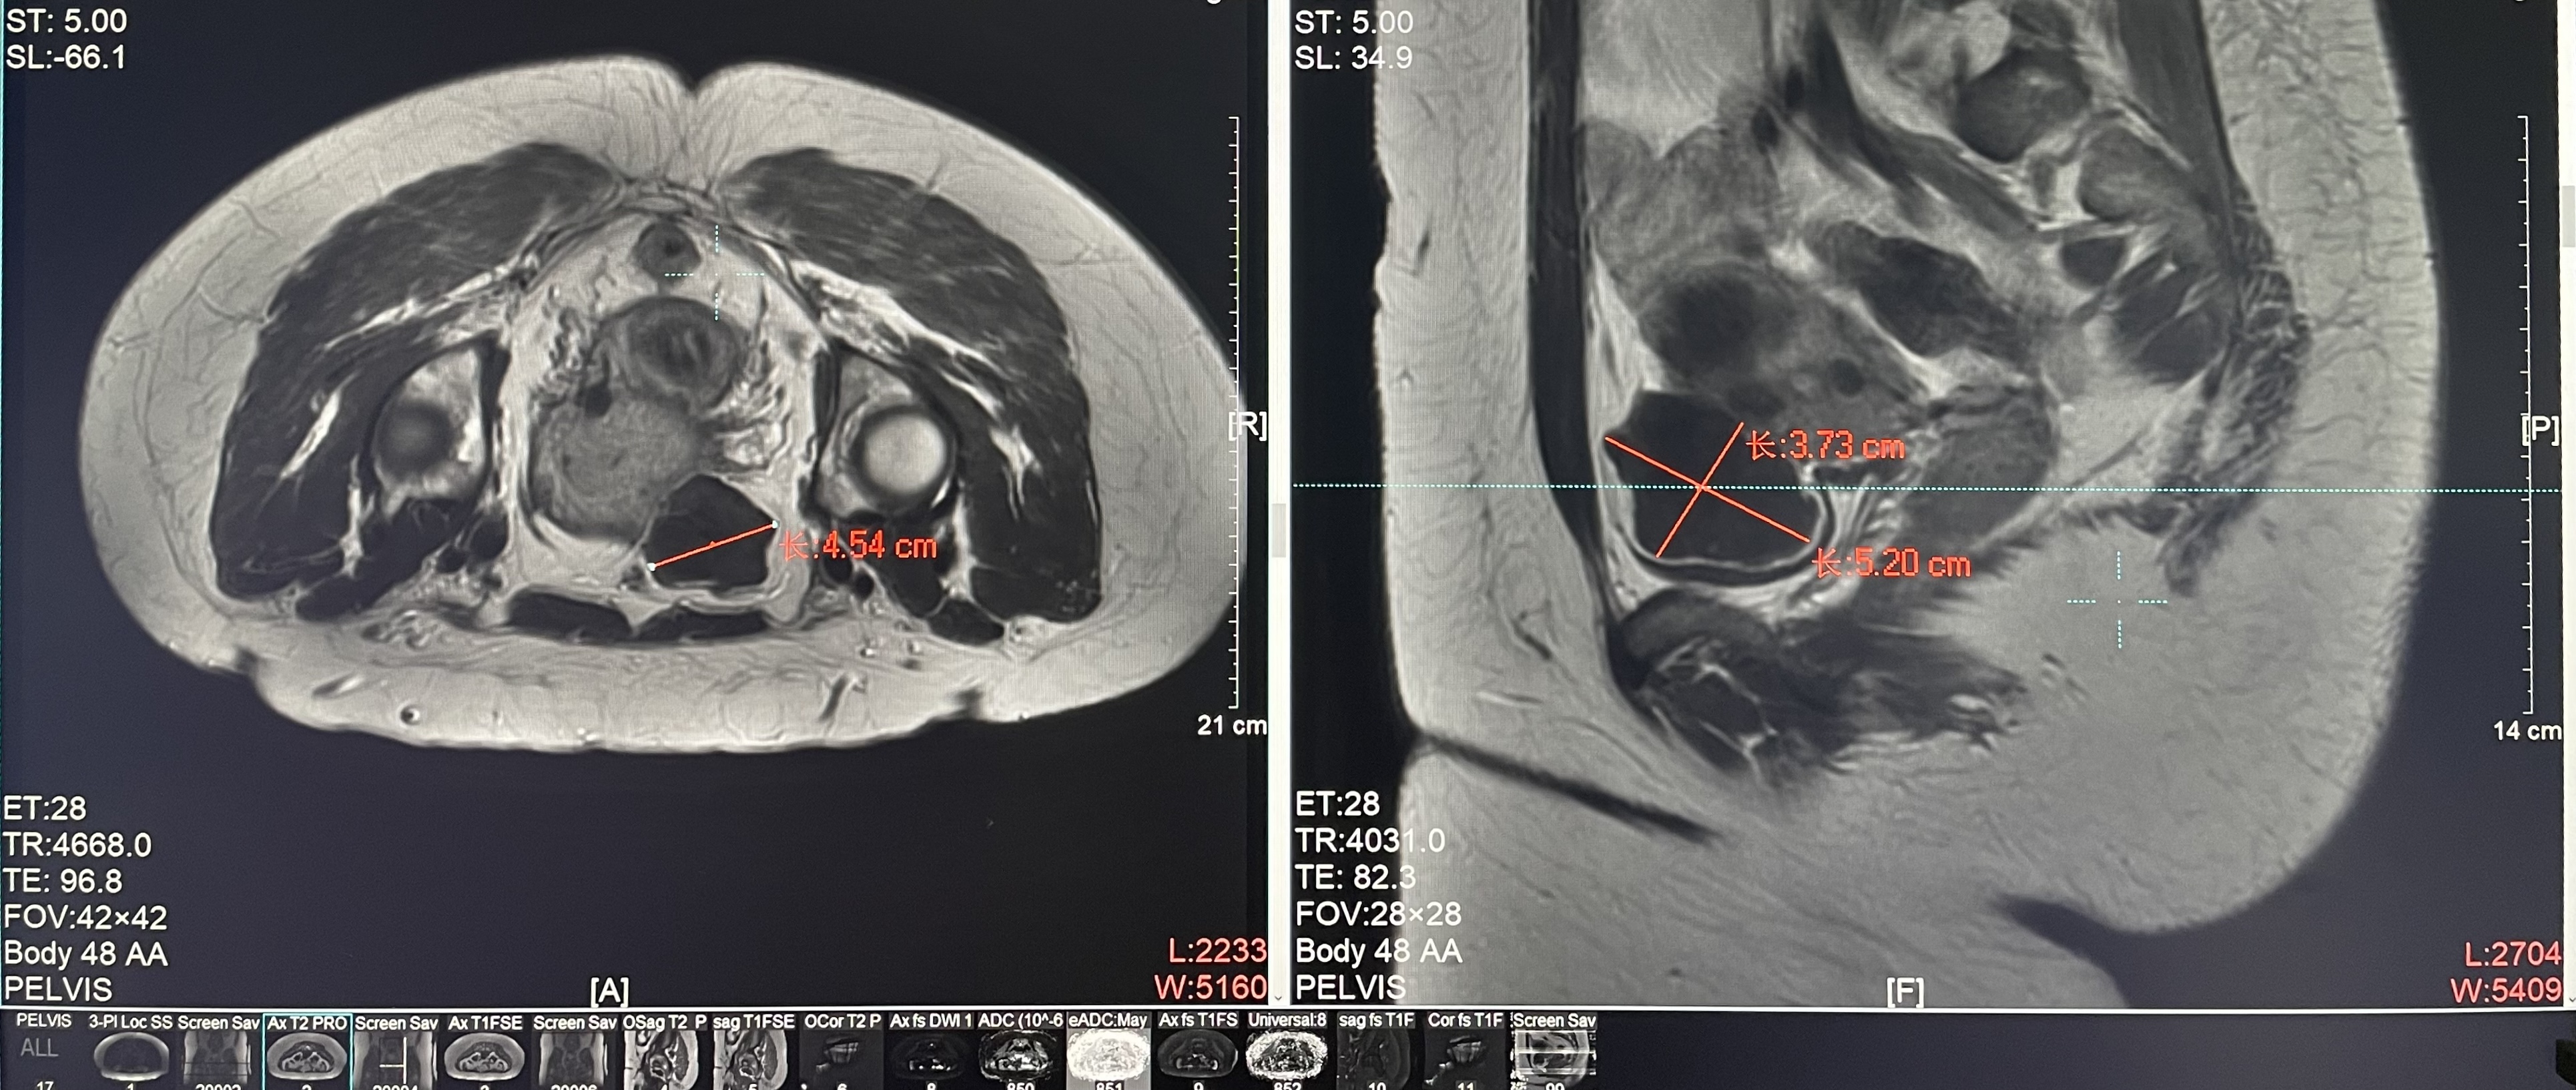

子宮腺肌癥

患者信息:女,38

診斷:子宮腺肌癥

病灶尺寸:約為40*37*40mm

ROT深度:病灶的ROT中心距離皮膚45mm

術后評估:術后造影增強圖像顯示消融區(qū)域(右側)與病灶區(qū)域(左側)重合度較好,非灌注區(qū)域連續(xù)且一致。

結論:對該病灶具有非常好的消融效果,治療過程中,溫度上升曲線符合預期,每個被治療的靶點240CEM區(qū)域體積較大、外形飽滿、連續(xù)。病灶消融良好,NPV體積比約80.6%。